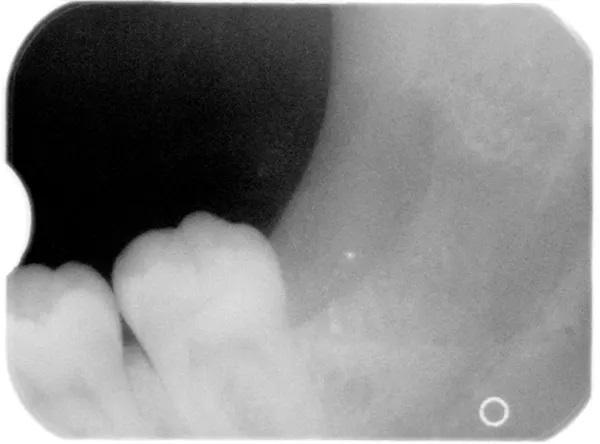

На панорамной рентгенограмме был обнаружен пораженный левый третий моляр нижней челюсти с тремя корнями и аномально большой коронкой (Фото 1). Необычная морфология зуба позволяла предположить, что это был случай сращения третьего моляра со сверхкомплектным зубом (то есть четвертым моляром).

Фото 1: Панорамная рентгенограмма, на которой виден “двойной зуб” в положении левого нижнего импактного третьего моляра.